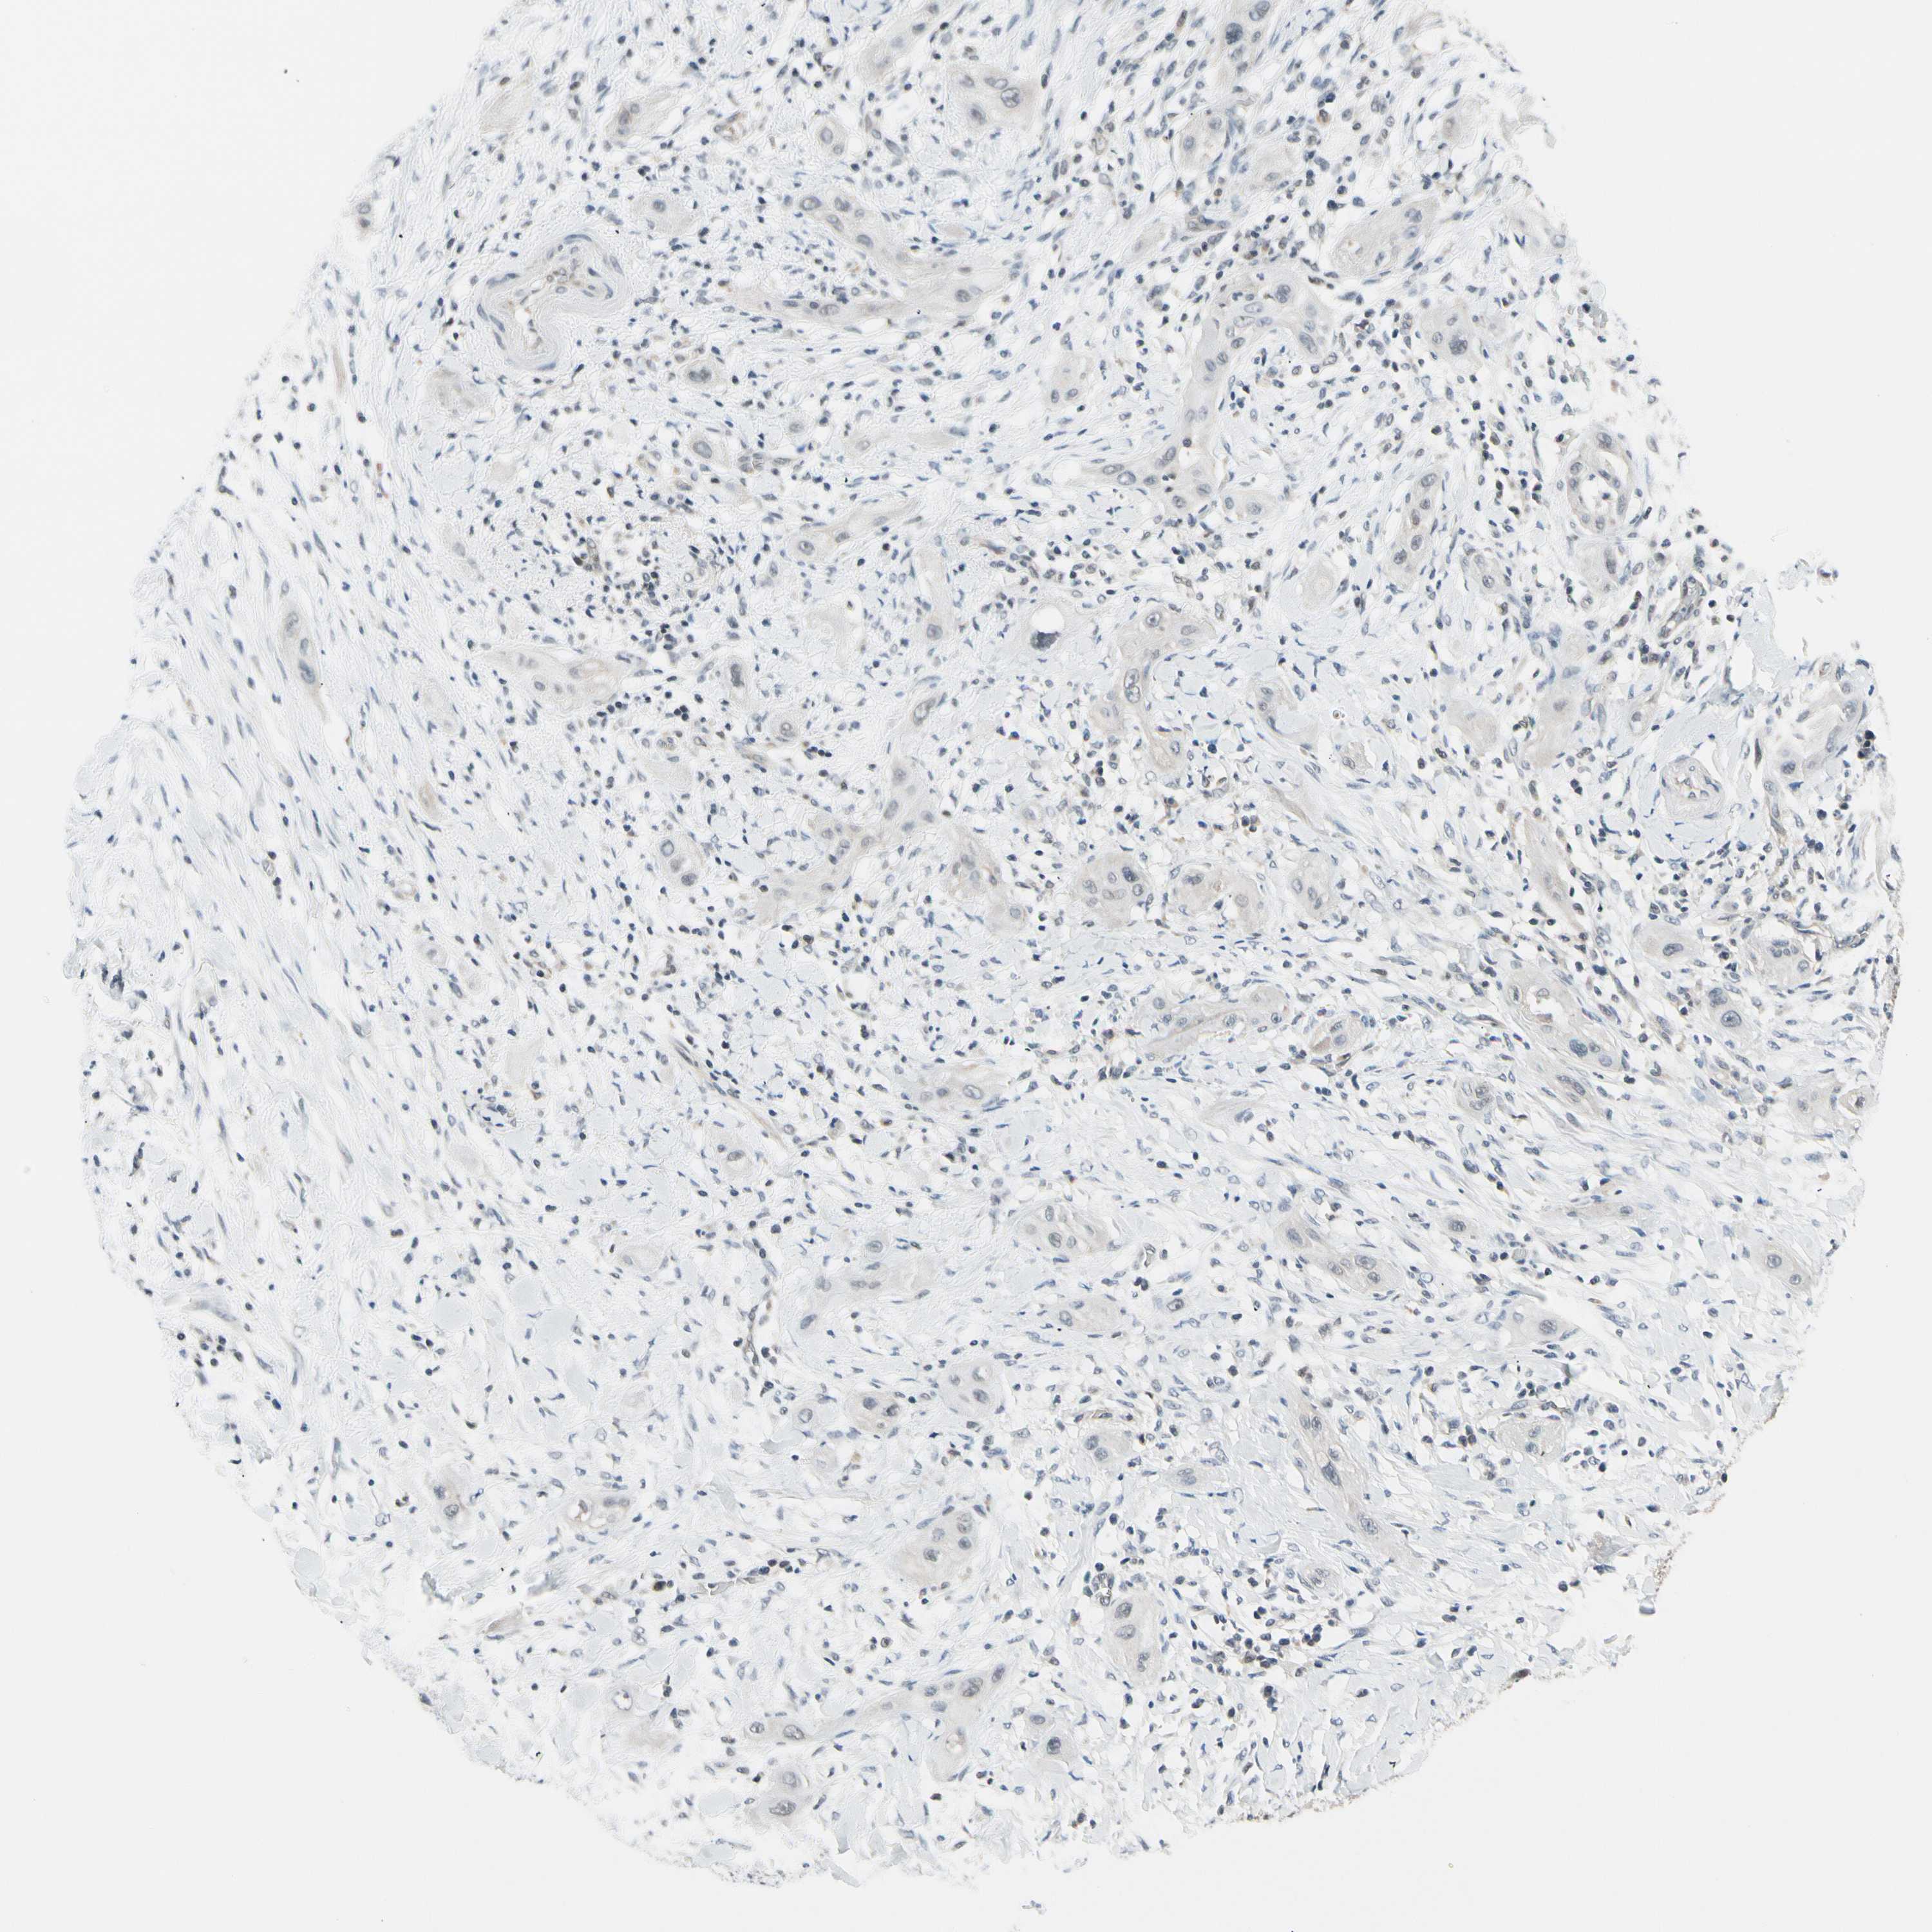

CANCER LUNG CANCER Show tissue menu

LUAD TCGA LUAD VALIDATION LUSC TCGA LUSC VALIDATION PROTEIN LUAD CPTAC PROTEIN LUSC CPTAC PROTEIN EXPRESSION

ANTIBODIES

AND

VALIDATION